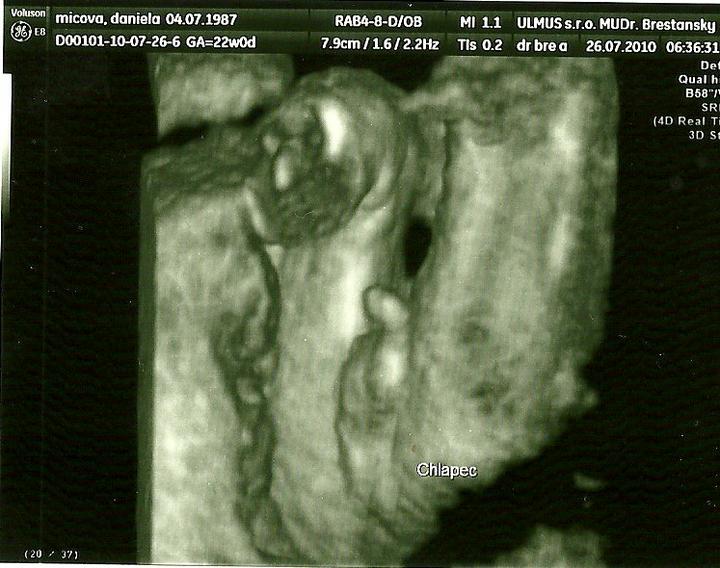

juchuu uz som doma.Super stuplik rastie ako z vody a aky je uz veliky:Daj rucicky,nozicky paraada :D zevraj bude mudry/a,lebo ma velku hlavku chichi :D:Daka som rada ze som ho zase videla 🙂

zajtra ideme na sono .... 🙂